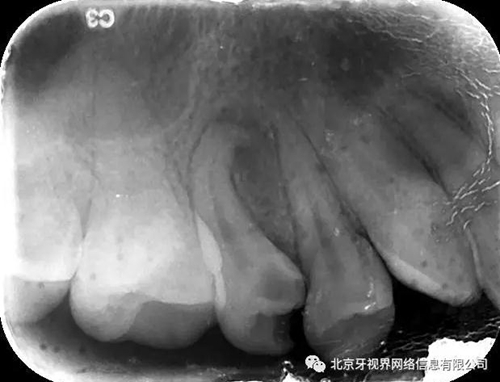

輔助檢查:15根尖周低密度影像,根尖1/3向近中彎曲

(1)15根尖周低密度影像結(jié)合查體診斷根尖周炎,根尖中下段明顯彎曲,能否疏通全長(zhǎng),順利抵達(dá)根尖區(qū)為術(shù)者首要考慮。

最后附帶近期彎曲根管的圖片